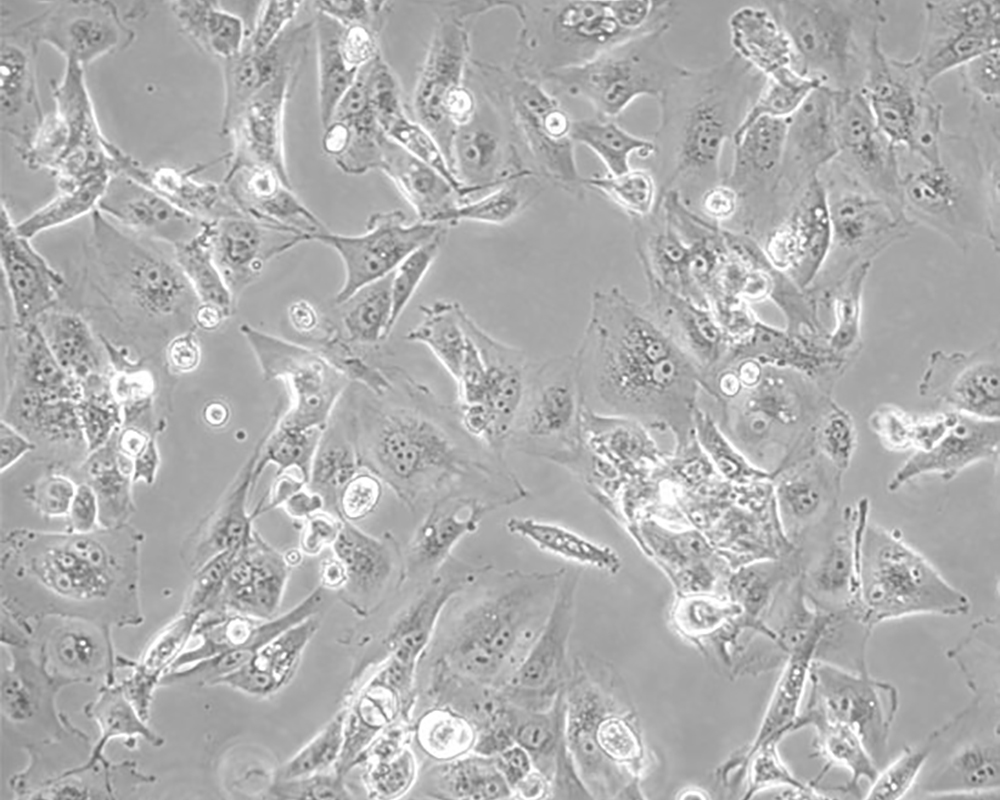

Caki-1

產品名稱 Caki-1

中文名稱 人腎透明細胞癌皮膚轉移細胞

組織來源 腎透明細胞癌;皮膚轉移;男性

生長特性 adherent

形態特征 epithelial

細胞描述 該細胞超微結構中包含許多微絨毛、少許微絲、許多小線粒體、發達的高爾基休和內質網、許多脂滴和多層體、次級溶酶體,沒有發現病毒顆粒。